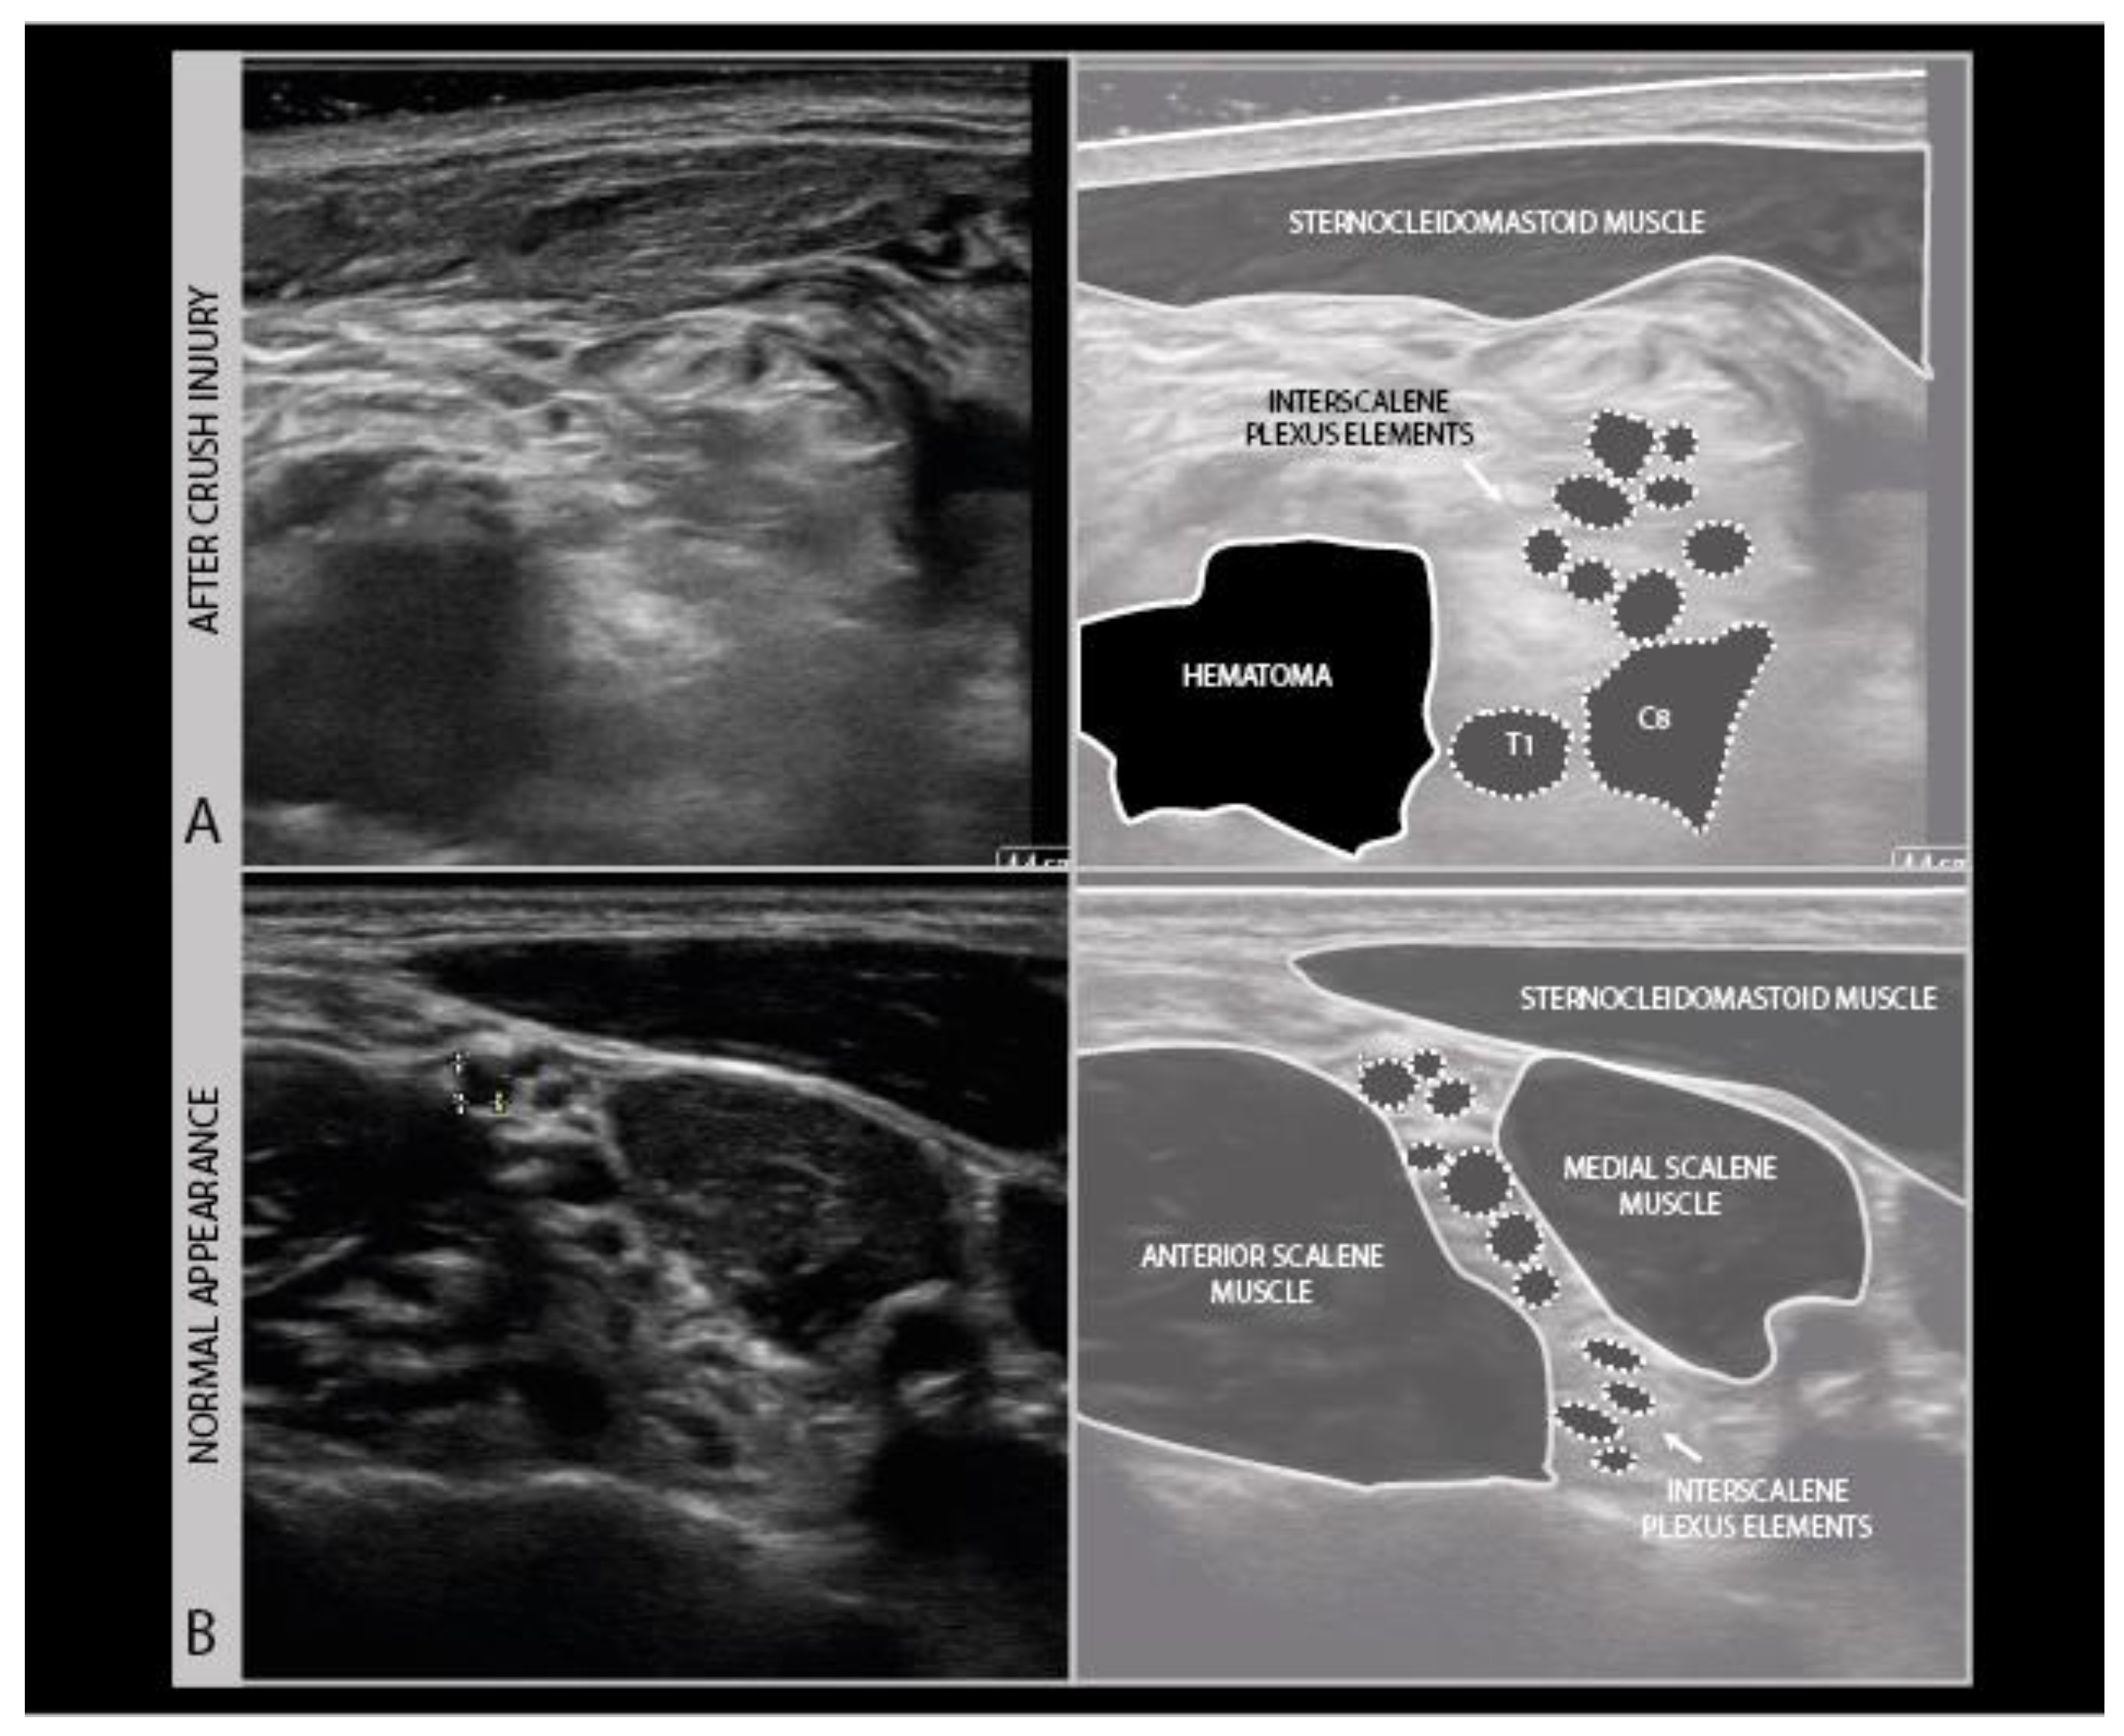

Ultrasound of fresh wound areas may be complicated by hematoma, giving a diffuse grayish shadowing of the image (Figure 12), and a loss of recognizable anatomical features (Figure 11 B).

Figure 12.

Right brachial plexus trauma with costoclavicular crush injury on day 1: hematoma with swollen C6–C7–C8–T1 elements (A) and normal interscalene plexus (B) for comparison.